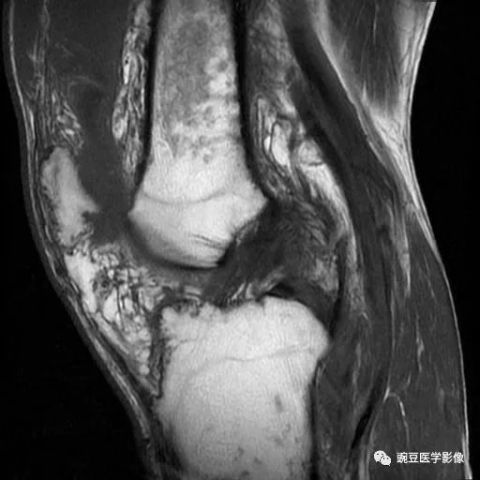

浮髌试验阳性,左膝关节MR示大量异常改变

480x480 - 26KB - JPEG